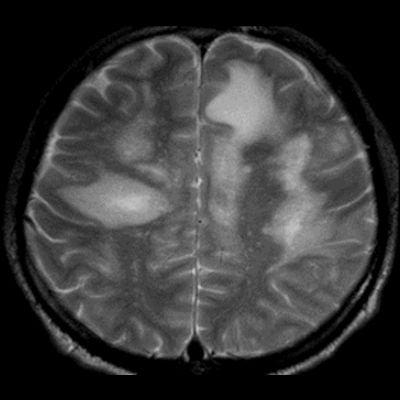

- Bilateral asimetrik subkortikal ve derin beyaz cevherde T1 ağırlıklı görüntülerde belirgin hipointens (oklar), T2A görüntülerde hiperintens (oklar), gri cevhere bakan kesimi düzgün (oklar), DAG’de hiperintens (ok) lezyonlar izlendi. Lezyonlarda T2/FLAIR uyumsuzluğu vardı (ok). Serebellar beyaz cevherde dentat nukleusu koruyan hilal işareti görüldü (ok başı). SWI sekansta sol motor kortekste hipointens kronik glioinflamatuar reaksiyon ile uyumlu sinyal değişikliği izlendi (ok başı).

- Çoğunlukla subkortikal beyaz cevherde ve U fiberlerde, asimetrik, genelde kitle etkisi yapmayan ve kontrastlanmayan demiyelinizan lezyonlar görülür. Korteks ve derin gri cevher tutulumu daha nadirdir.

- PML lezyonları, T1A görüntülerde belirgin hipointenstir. Gri cevhere bakan yüzleri keskin olup T2/FLAIR uyumsuzluğu önemli özelliğidir.